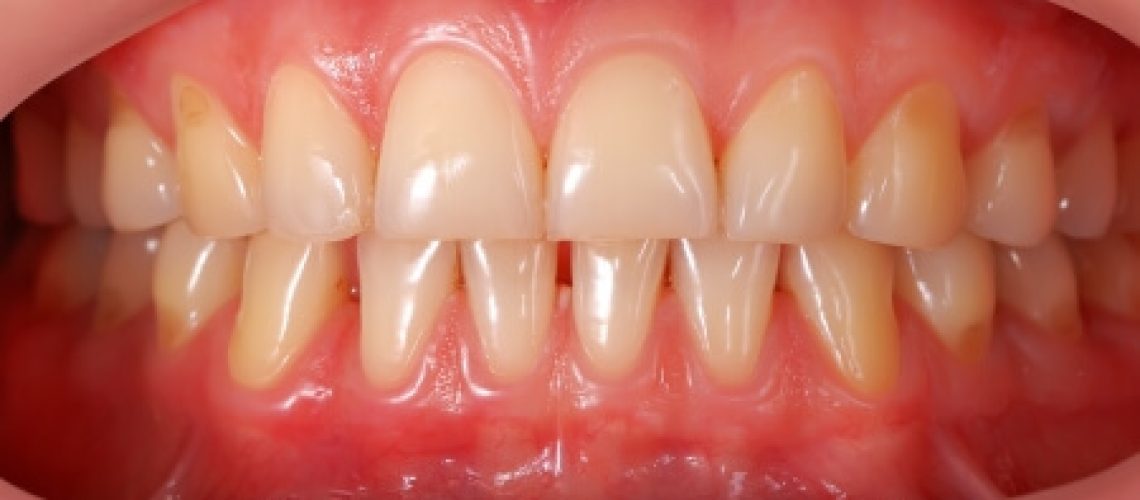

Gezond tandvlees is roze. Wanneer er sprake is van een ontsteking van het tandvlees ook wel gingivitis genoemd, is het tandvlees roder van kleur. Indien gingivitis niet tijdig wordt aangepakt gaat dit over in peridontitis. Hierbij is niet alleen het tandvlees ontstoken, ook trekt het tandvlees zich terug. In een vergevorderde stadium neemt ook het botweefsel af en ontstaan er zogenaamde pockets. Dit zijn smalle ruimtes tussen het tandvlees en de tanden zoals in het plaatje hieronder ook is te zien.

Er zijn twee belangrijke aspecten om erop een eenvoudige manier achter te komen of jouw tandvlees gezond is. De eerste is de kleur. Gezond tandvlees is roze. Des te meer het tandvlees ontstoken is des te roder de kleur.. Het belangrijkste aspect is wel dat gezond tandvlees niet bloed.